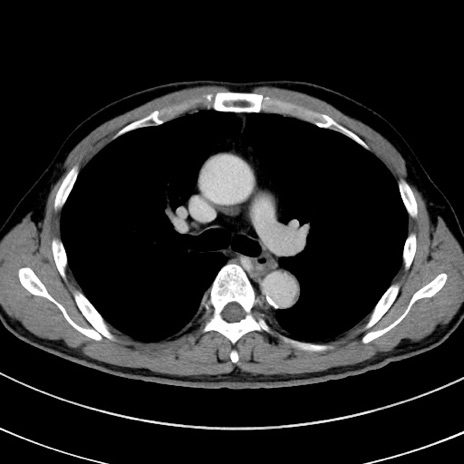

症例8(横断像)

【症例】 60歳代男性

【主訴】 黒色吐物

【現病歴】 4日前から嘔気自覚、2日前の朝食後にも嘔気あり、自分で手で嘔吐反射起こし嘔吐したところ血が混ざっていたため受診。

【既往歴】 5年前汎発性腹膜炎を伴う急性虫垂炎で手術、高血圧、前立腺肥大症、高脂血症

【身体所見】 腹部正中に手術癩痕あり 腹部平坦・軟圧痛なし膨満感あり

【データ】WBC 8400、CRP 4.54